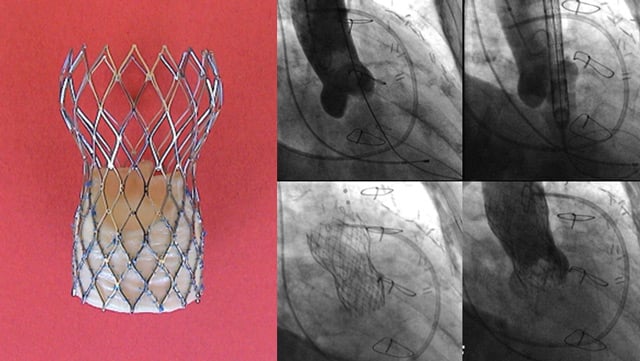

Amulet IDE: Amplatzer Amulet Left Atrial Appendage Occluder RCT - 12-Month Closure Follow-up

04 Nov 2021

Ali Nazmi Calik reviews Amulet IDE, a prospective, randomized, multi-center and active-control trial designed to compare the Amulet and Watchman 2.5 devices in a head-to-head fashion, and presented by Dhanunjaya Lakkireddy during TCT 2021.